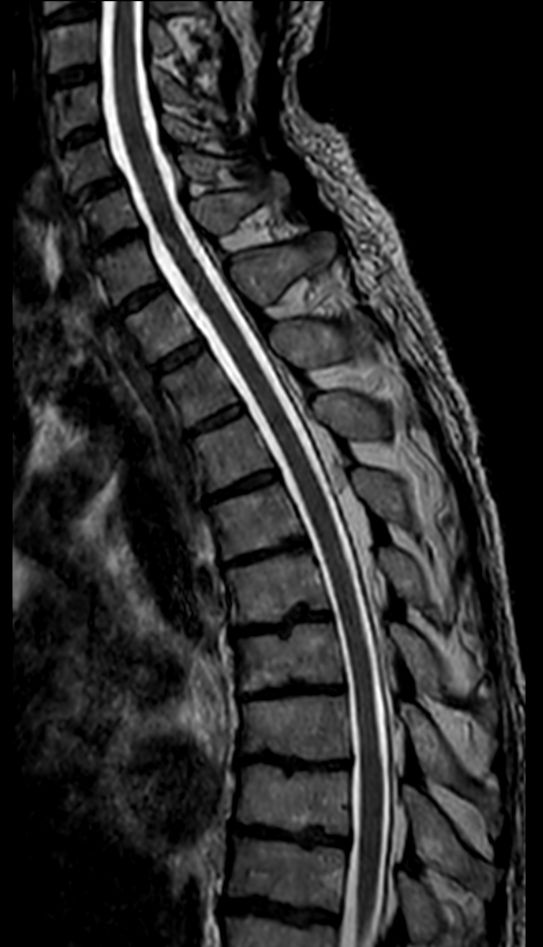

Sagittal T1w TSE (2 stations)Compressed SENSE

Sagittal T2w TSE (2 stations)Compressed SENSE

Sagittal STIR TSE (2 stations)Compressed SENSE

Sagittal 3D T2w TSE (SpineVIEW)Compressed SENSE